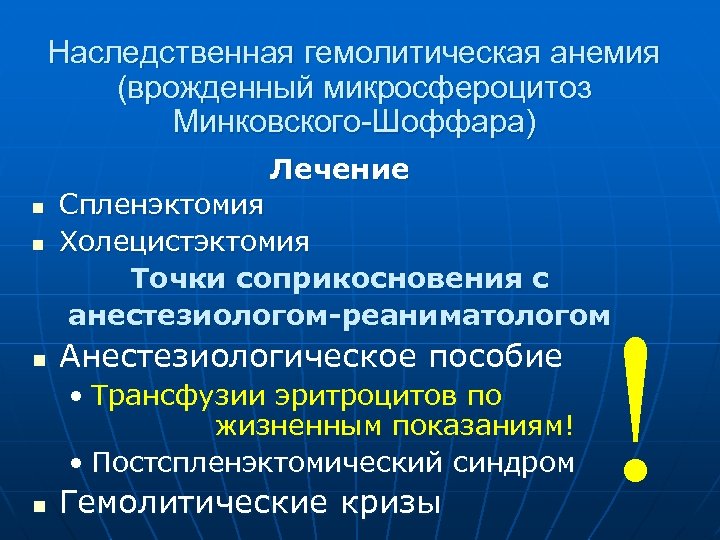

Наследственная гемолитическая анемия (врожденный микросфероцитоз Минковского-Шоффара) Лечение n n n Спленэктомия Холецистэктомия Точки соприкосновения с анестезиологом-реаниматологом Анестезиологическое пособие • Трансфузии эритроцитов по жизненным показаниям! • Постспленэктомический синдром n Гемолитические кризы !